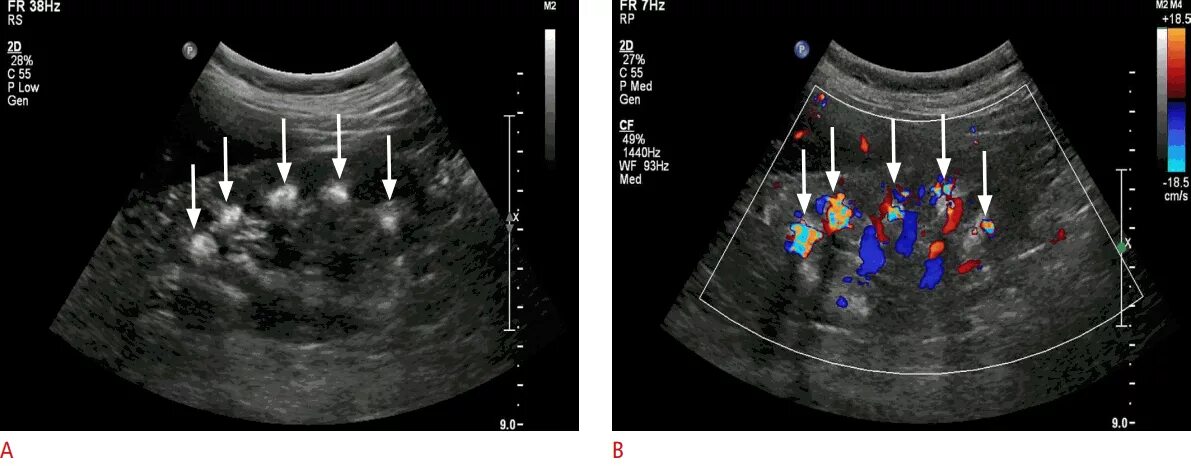

Синдром гиперэхогенных пирамид

Гиперэхогенные пирамиды в почках на узи. синдром гиперэхогенных пирамидок на узи. медуллярный нефрокальциноз почек узи. медуллярная губчатая почка узи.

Синдром гиперэхогенных пирамид на узи. синдром гиперэхогенных пирамид почек узи. медуллярная губчатая почка узи. гиперэхогенные пирамидки в почках на узи.